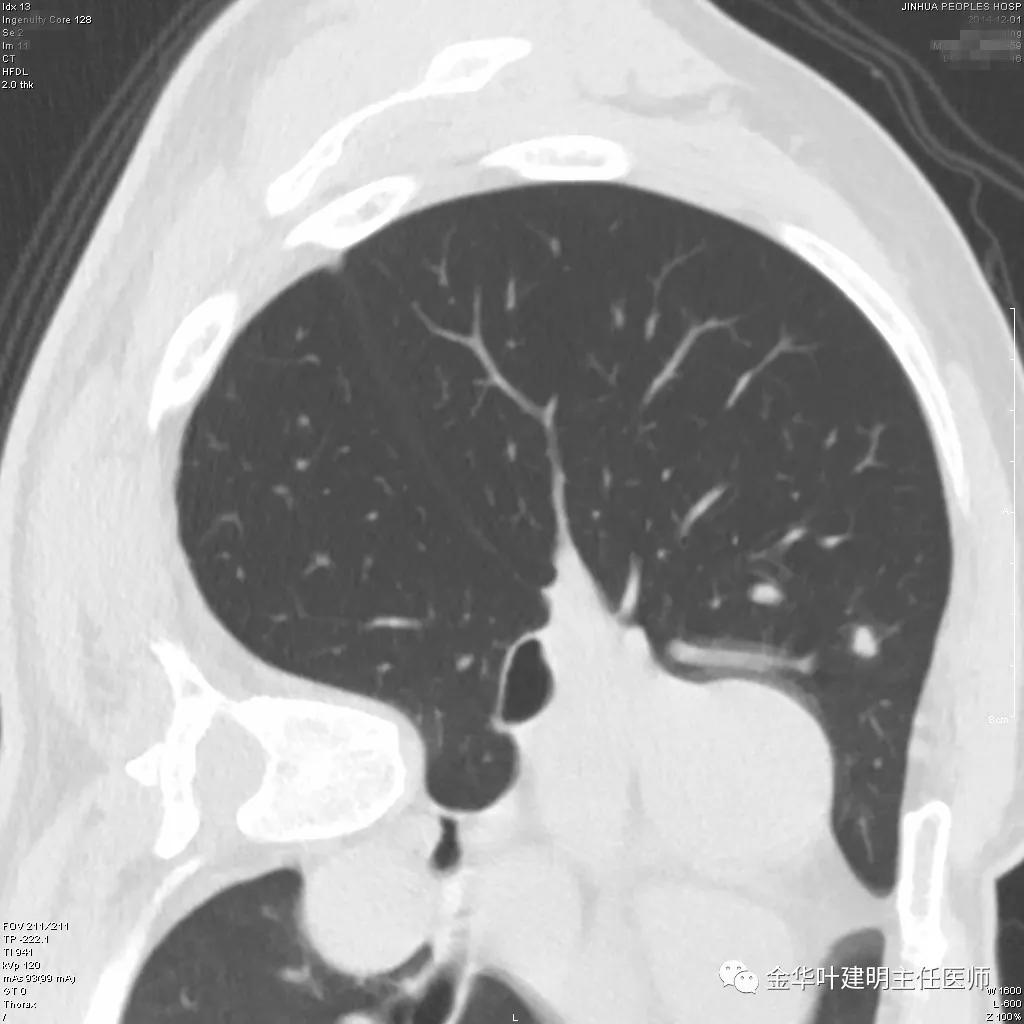

患者为48岁男性,检查发现左肺上叶实性结节,临床没有炎症表现,肿瘤指标不高,没有查过结核及隐球菌荚膜抗原试验或G试验、M试验等。我们先来看其前一个月时的平扫影像:

上图示有血管征,与病灶关系较密切

上图示血管与病灶临近,但没有被病灶牵拉从而进入病灶

我们见左上实性病灶,主病灶旁有卫星灶,有血管进入,但也有贴边走行,边缘略显模糊,膨胀感与细毛刺不明显,收缩力也不明显。下面是其靶扫描的片子: